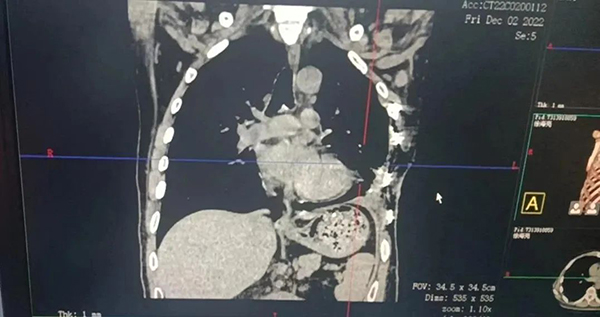

术后影像学表现